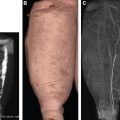

The most superficial layer where fluid accumulates is the subepidermal lymphatic plexus, occupying a papillary and reticular dermis with a thickness of 200 to 300 microns (Fig. 25-1). However, the volume of fluid in this plexus is negligible, compared with the volume of the subcutaneous tissue fluid, and does not exceed 2% to 3% of the total tissue fluid retained in soft tissues. The bulk (95%) of mobile tissue fluid accumulates in the subcutaneous tissue, forming artificial, partly interconnected spaces (Fig. 25-2). These spaces are located between fat globules, fibrous bundles, and around small veins.

The formation of large lakes of tissue fluid can be explained by the presence of lax connective tissue in these regions, its high compliance and subsequently low resistance to fluid flow. Tissue fluid channels form, which mostly are narrow longitudinal spaces between the normal fascial fibrous elements around and in the hypertrophic muscular fascia of the calf, sometimes reaching 2 cm in diameter. The hydraulic conductivity of these structures is high because of the linear positioning of fibers. 2 The volume of fluid accumulating in the tissue spaces and calculated from the densitometric readings of the stained tissues can be as high as 40% to 50% of the total tissue volume 1 (Fig. 25-3, A). Anatomic images of the skin and subcutis in lower and upper limb lymphedema show that the thickness of edematous tissues is 1 to 10 cm or more (Fig. 25-3, B). (The staging system referred to in this chapter is that of W.L. Olszewski. 14 ) This information raises the following question: How much massaging force should be applied to affect the deepest edematous tissue layers? In this chapter, we attempt to answer this question.